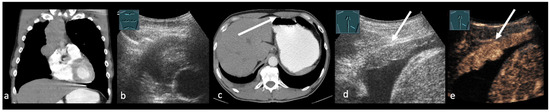

Emerging Role of Transcutaneous Ultrasound in the Diagnostic of Lung Cancer

by Corinna Trenker-Burchert, Marius Dohse, Hajo Findeisen, Andreas Schuler and Christian Görg

Cancers 2025, 17(23), 3873; https://doi.org/10.3390/cancers17233873 - 2 Dec 2025

Lung cancer is one of the most commonly diagnosed malignancies worldwide and continues to be a leading cause of cancer-related mortality. Precise staging is crucial for predicting outcomes and directing treatment decisions. Current international guidelines mainly recommend imaging techniques like CT and PET-CT, [...] Read more.

Lung cancer is one of the most commonly diagnosed malignancies worldwide and continues to be a leading cause of cancer-related mortality. Precise staging is crucial for predicting outcomes and directing treatment decisions. Current international guidelines mainly recommend imaging techniques like CT and PET-CT, with limited references to transcutaneous ultrasound, which is only suggested in particular clinical cases. Ultrasound provides real-time imaging, high resolution in near-field structures, and the ability to assess thoracic wall infiltration, supraclavicular and cervical lymph nodes, pleural effusions, and metastatic lesions. Furthermore, ultrasound-guided biopsies can enable quick and safe histological confirmation of accessible lesions. Based on these advantages and a review of current literature, we propose that integrating ultrasound into staging algorithms could improve diagnostic efficiency, decrease invasive procedures, and support prompt treatment planning. We also highlight the need for further research in this area. Full article

Show Figures

Figure 1